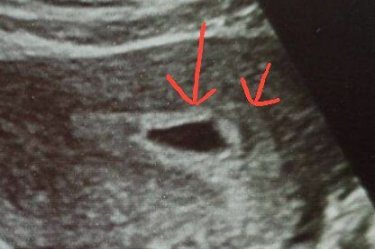

Похоже будто бы появляется второе плодное яйцо или всё-таки на отслойку? Узи 5 недель У кого как было?

На 5 неделях УЗИ редко можно точно определить наличие второго плодного яйца. Обычно на этом этапе видна только одна плодная зона. Отслойка тоже маловероятна, если нет кровотечения или боли. Для уточнения лучше повторить УЗИ через 1-2 недели.

Не похоже ни на отслойку ни на 2 плодное яйцо.